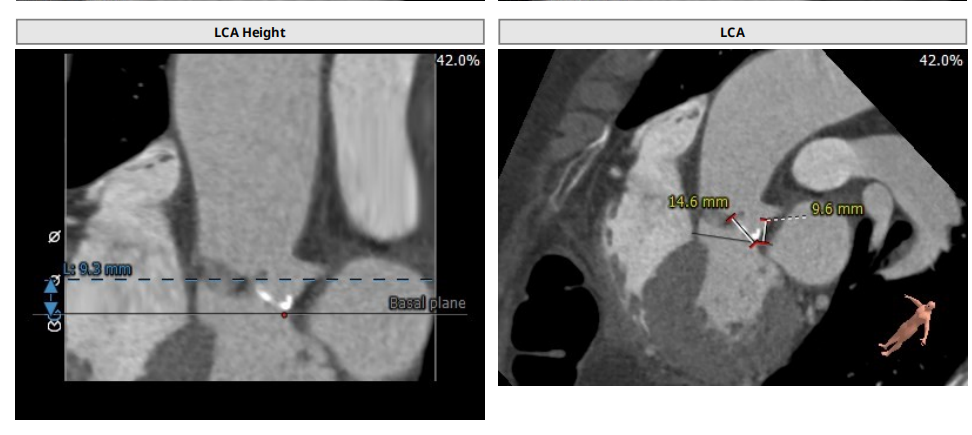

此次手术对象为一名老年女性患者,身高155cm,体重51kg。因“胸闷憋气,咳嗽半年”入院,心超诊断主动脉瓣重度狭窄伴轻度关闭不全,二尖瓣轻度反流,三尖瓣轻-中度反流,肺动脉瓣轻度反流,室间隔心肌肥厚、升主动脉扩张,左室舒张功能降低。既往冠心病20年,平素间断服用“阿司匹林”等药物。术前CT显示患者主动脉瓣口面积352.7 mm²,瓣环平均直径21.4mm,瓣周长68.3 mm;LVOT面积320.4 mm²,平均直径20.8 mm。江磊教授于术后采访中点明了本例TAVR手术操作棘手之处。江教授指出,从术前影像学来看,病人为三叶瓣,这是其一;此次手术最主要的难点则在于病人的左冠较低,而TAVR手术中对于冠脉的最低要求应在瓣环上1公分左右,此例手术患者又恰好处于友好临界值上0.9cm。因此,为规避冠脉阻塞风险,江磊教授团队决定采用SAPIEN 3球扩式瓣膜。“如果使用自膨式瓣膜,冠脉阻塞风险相对来说高一些,而SAPIEN 3是一款球扩式瓣膜,可以最大程度的避免左冠闭塞的风险,同时考虑到患者家庭诉求,我们在综合考量下选择SAPIEN 3瓣膜,事实也证明它的确能发挥这样的效用。”